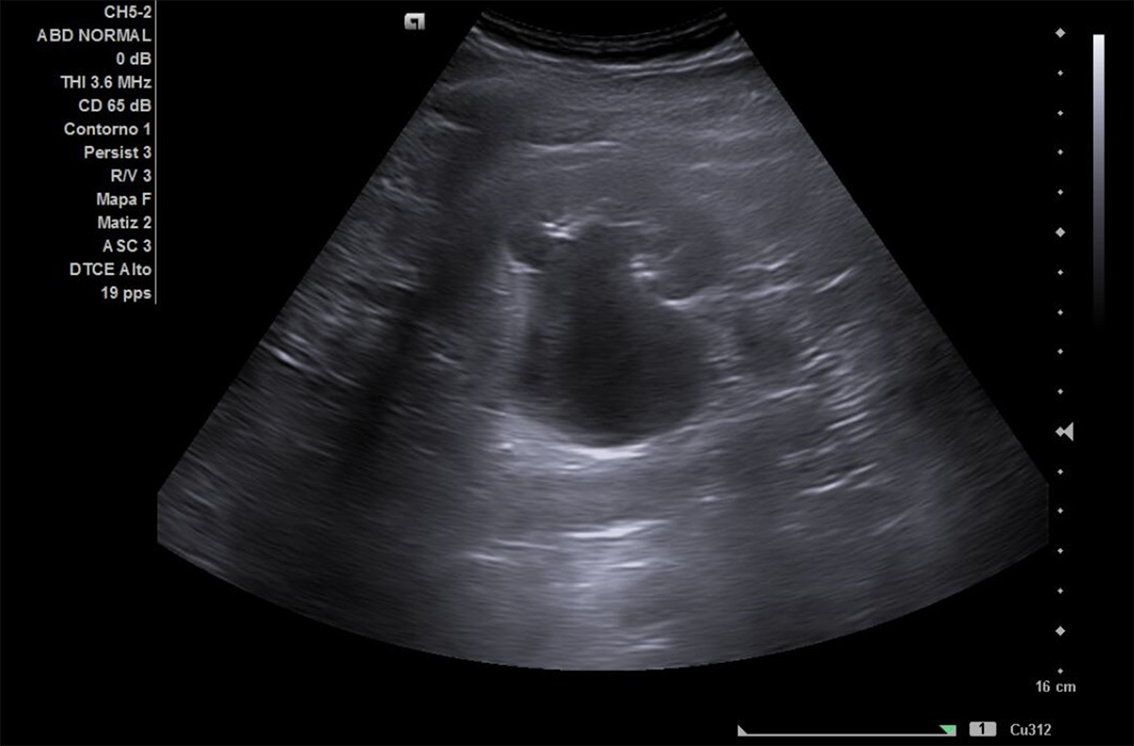

Se realiza ECO POCUS en la que se aprecia riñón derecho de morfología y tamaño normal. Riñón izquierdo con hidronefrosis grado III. A nivel de vejiga, bien replecionada se aprecia masa a nivel de pared izquierda adyacente a unión ureterovesical de 1.8 x 2,7 cm Ausencia de jet izquierdo.